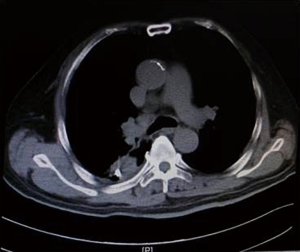

As illustrated in Table 3, tumors were significantly reduced in all 6 patients after the implantation of radioactive particles. A typical case can be seen in Figures 4,5.

As shown in Figure 7 and Figure 3, there were 2 CRs and 4 PRs after follow-up for 1 month, indicating a response rate (RR) of 6/6, and a disease control rate (DCR) of 6/6; six patients were followed up for 6 months, including one patient who refused follow-up visit (still alive),while the other 5 patients were followed up regularly, including 3 CRs and 2 PRs; five patients were followed up for 12 months, including 3 CRs, 1 PR and 1 PD, indicating an RR of 4/5, a DCR of 4/5, and a progression rate of 1/5; four patients were followed up for 18 months, including 3 CRs and 1 SD, indicating a RR of 3/4 and a DCR of 4/4; four patients were followed up for 24 months, including 1 patient who refused a follow-up visit (still alive), while the other 3 patients were still followed up regularly; there were still 4 patients who were followed up for 30 months, including 1 patient who refused follow-up visit (alive) and 3 patients who were followed up on a regular basis; one patient was followed up for 36 months and had a recurrence of primary lesion, with the response being evaluated as PD. In addition, Figure 7 shows that patient E achieved significant response after implantation of 125I particles, and the response was evaluated as CR 1 month after implantation (Figures 8,9); however, the primary lesion recurred and was enlarged with left lung metastasis in month 12 (Figures 10,11), whereupon the response was evaluated as PD. The patient was given CT-guided implantation of 125I radioactive particles again for treatment of the recurrent lesion. The repeated pulmonary CT after re-implantation showed significant reduction of tumor (reduction rate 27.32%), as shown in Figure 12, and the response was subsequently re-evaluated as SD.

Other relevant studies have shown a unique advantage of implantation of radioactive particles in the treatment of lung cancer. In a study by Lu et al. (10), 15 patients with obstructive pneumonia caused by central type lung cancer were given a bronchoscopic implantation of 125I radioactive particles, and followed up in months 2, 6, 12, 18 and 24 after implantation. The median survival was 15.6 months, and the one-year lung recruitment rate was 80.0%, which significantly improved the quality of life. To compare, in our study’s response evaluation from regular follow-up of patients who received the CT-guided implantation of radioactive 125I, it was found that the tumors had significantly shrunk in all 6 patients. Typical cases are illustrated in Figures 4 and 5, and as can be seen in Figure 6, the most obvious reduction of tumor was seen in the 6th month of follow-up. In the 5 patients who were followed up, there were 3 CRs, indicating an RR of 5/5 (100%) and a DCR of 5/5 (100%). This shows that the implantation of radioactive particle achieved the best response within 6 months in the treatment of early lung cancer. In addition, as Figure 3 shows, 5 patients were followed up 1 year after implantation and had a survival rate of 5/5 (100%), 4 patients were followed up 2 years after implantation and had a survival rate of 4/4 (100%), and the longest time after enrollment was up to 3 years and 5 months; at the time of writing, this patient is still alive. The observations above demonstrate the significant efficacy of the implantation of 125I radioactive particles in treatment of early lung cancer.